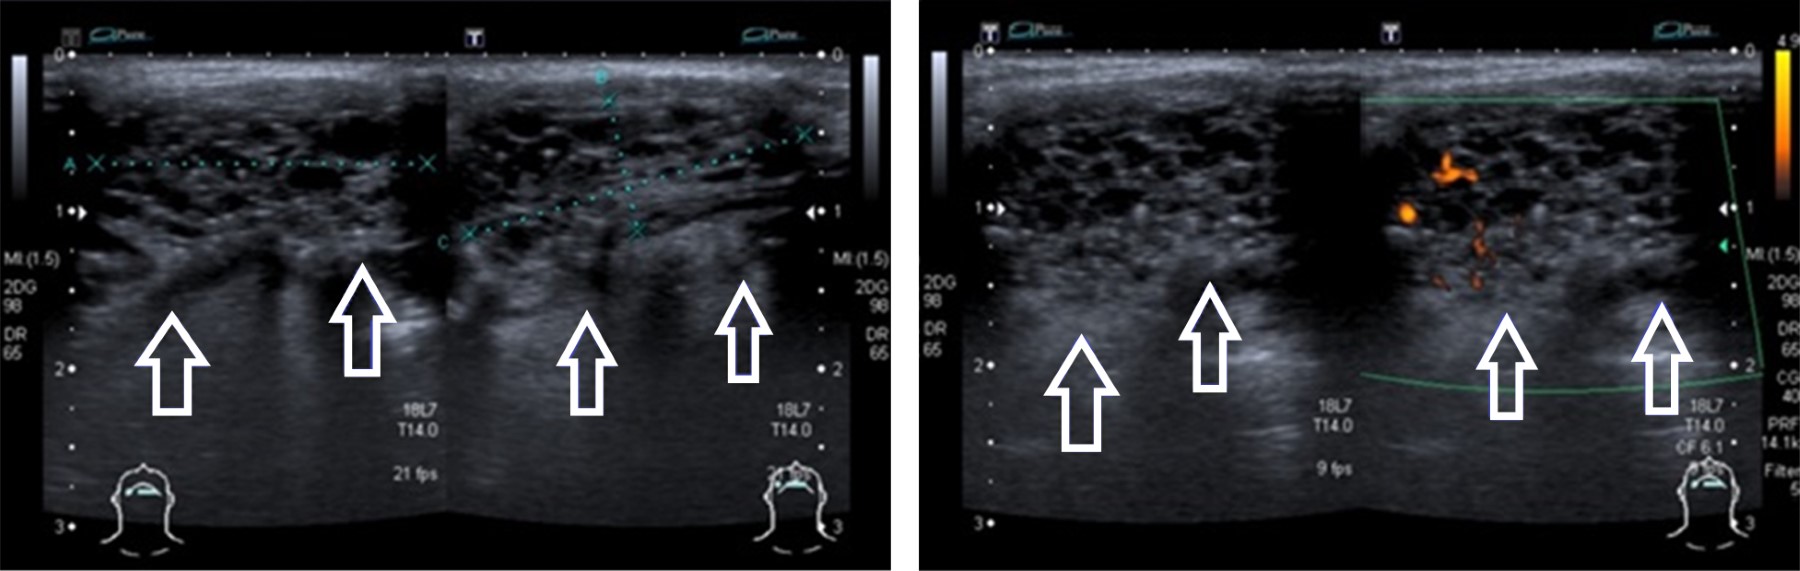

Se indicó un nuevo ultrasonido en el que se localizó una lesión en línea media cervical, sublingual, de morfología ovalada, de bordes bien definidos, con medidas de 21 × 9 × 22 mm, el volumen aproximado de 2.2 cm3; heterogénea a expensas de múltiples imágenes hipoecogénicas redondeadas, de bordes bien definidos. A la aplicación de Doppler color se presentó flujo intralesional, concluyendo: tiroides ectópica sublingual, con presencia de múltiples quistes coloides (Figura 1).

Figura 1